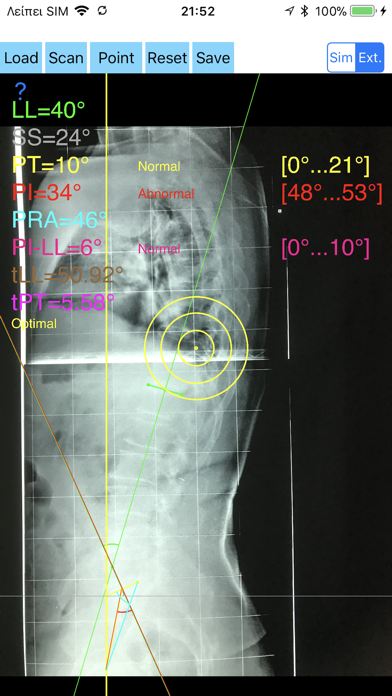

1. -By marking few points at the image of X-ray, the App calculates and offers a very convenient way to determine the most accurate possibly way at once, Pelvic incidence (PI), Sacral slope (SS), Pelvic Tilt (PT), Lumbar lordosis (LL), thoracic kyphosis, PI–LL Pelvic incidence Angle (PI) minus Lumbar lordosis Angle (LL) PI–LL, theoretical normal pelvic tilt (tPT),theoretical normal L1-S1 lumbar lordosis (tL1S1), Pelvic Radius Angle (PRA).

2. Radiographic parameters to evaluate objectively the spinopelvic sagittal balance are Pelvic incidence (PI), Sacral slope (SS), Pelvic Tilt (PT), Lumbar lordosis (LL).

3. -The app offers theoretical value estimation this is particularly useful because a sensible difference between theoretical value and measured value reveals a compensation phenomenon if the pelvis tilt (PT) is higher than its theoretical value, then it is due to pelvis retroversion, which is a compensation phenomenon.

4. Knowing the theoretical value of Pelvis Tilt (PT) provided it is easy to understand that a sensible difference between theoretical value and measured value is a compensation phenomenon.

7. -Save the planned images, for later review or consultation.The measured values are compared by normal reference databases and also data are exported as txt file, ready to print or to input as cells to excel for research.

8. The app offers a very convenient and accurate way to perform most common radiographic measurements for spine, at the spinopelvic juncture in a blink of an eye in front of your screen.

11. According to measured parameters the app categorises the severity of the imbalance of spine, in different stages: optimal or non optimal.